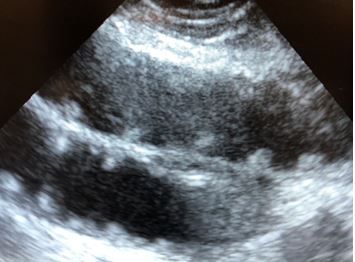

Initial diagnostic testing:

Bedside ultrasound